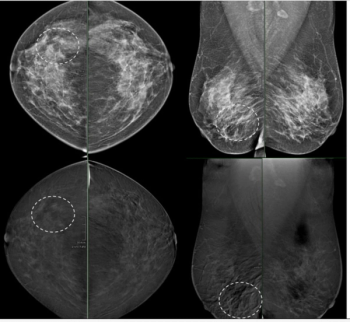

For women with dense breasts and negative mammograms, contrast-enhanced mammography and abbreviated MRI provided respective cancer detection rates of 19.2 per 1000 exams and 17.4 per 1000 exams, according to new research.